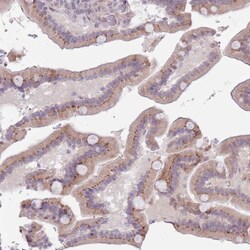

Supportive validation

- Submitted by

- Invitrogen Antibodies (provider)

- Main image

- Experimental details

- Immunohistochemical analysis of ZN576 in human duodenum using ZN576 Polyclonal Antibody (Product # PA5-62128) shows moderate cytoplasmic positivity in glandular cells.